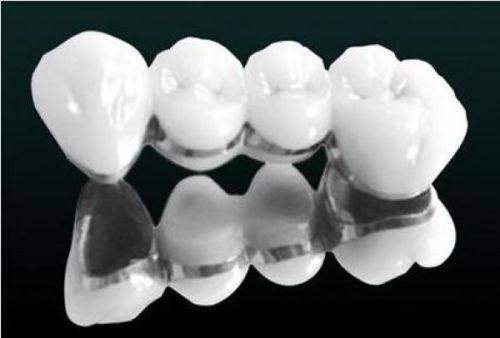

医院配备了一系列精良的医疗设备,如高频电刀、根管填充器、CBCT机、数字化口腔全景机、数字化口腔内窥镜、CBCT口腔全景检查设备、数字导板、数字化正畸设备等。 这些设备的应用,能够确保口腔疾病的诊断更加正确,治疗更加科学、精细。

在种植牙领域,合肥中诺口腔医院采用了北京3级中诺口腔医院研发的“立得用即刻种植”技术。 技术通过数字化3D技术实现种植手术的可视化、精控化,术前能够提前定位好种植体的植入位置、方向、深度等,轻松避开神经、血管等敏感区域,减少术中出血和并发症的风险。同时,该技术还独特地将植体呈“W”状植入牙槽骨,使植体更加稳固,手术耗时短且种植牙的使用寿命更长。